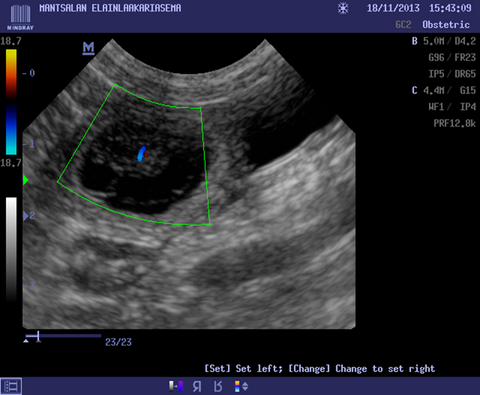

Regular Veterinary Check-ups: Schedule regular check-ups with your veterinarian to monitor the progress of the pregnancy, address any concerns, and ensure the mother's health.

Veterinary Care: Check-ups with a veterinarian are essential during pregnancy to monitor the health of both the mother and the puppies.